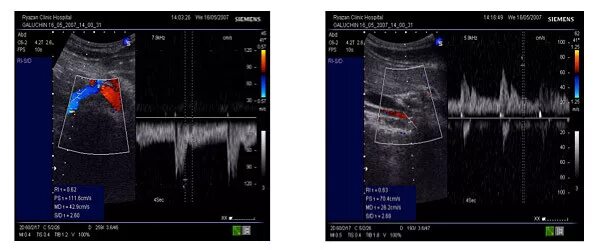

Диффузное изменение правой почки